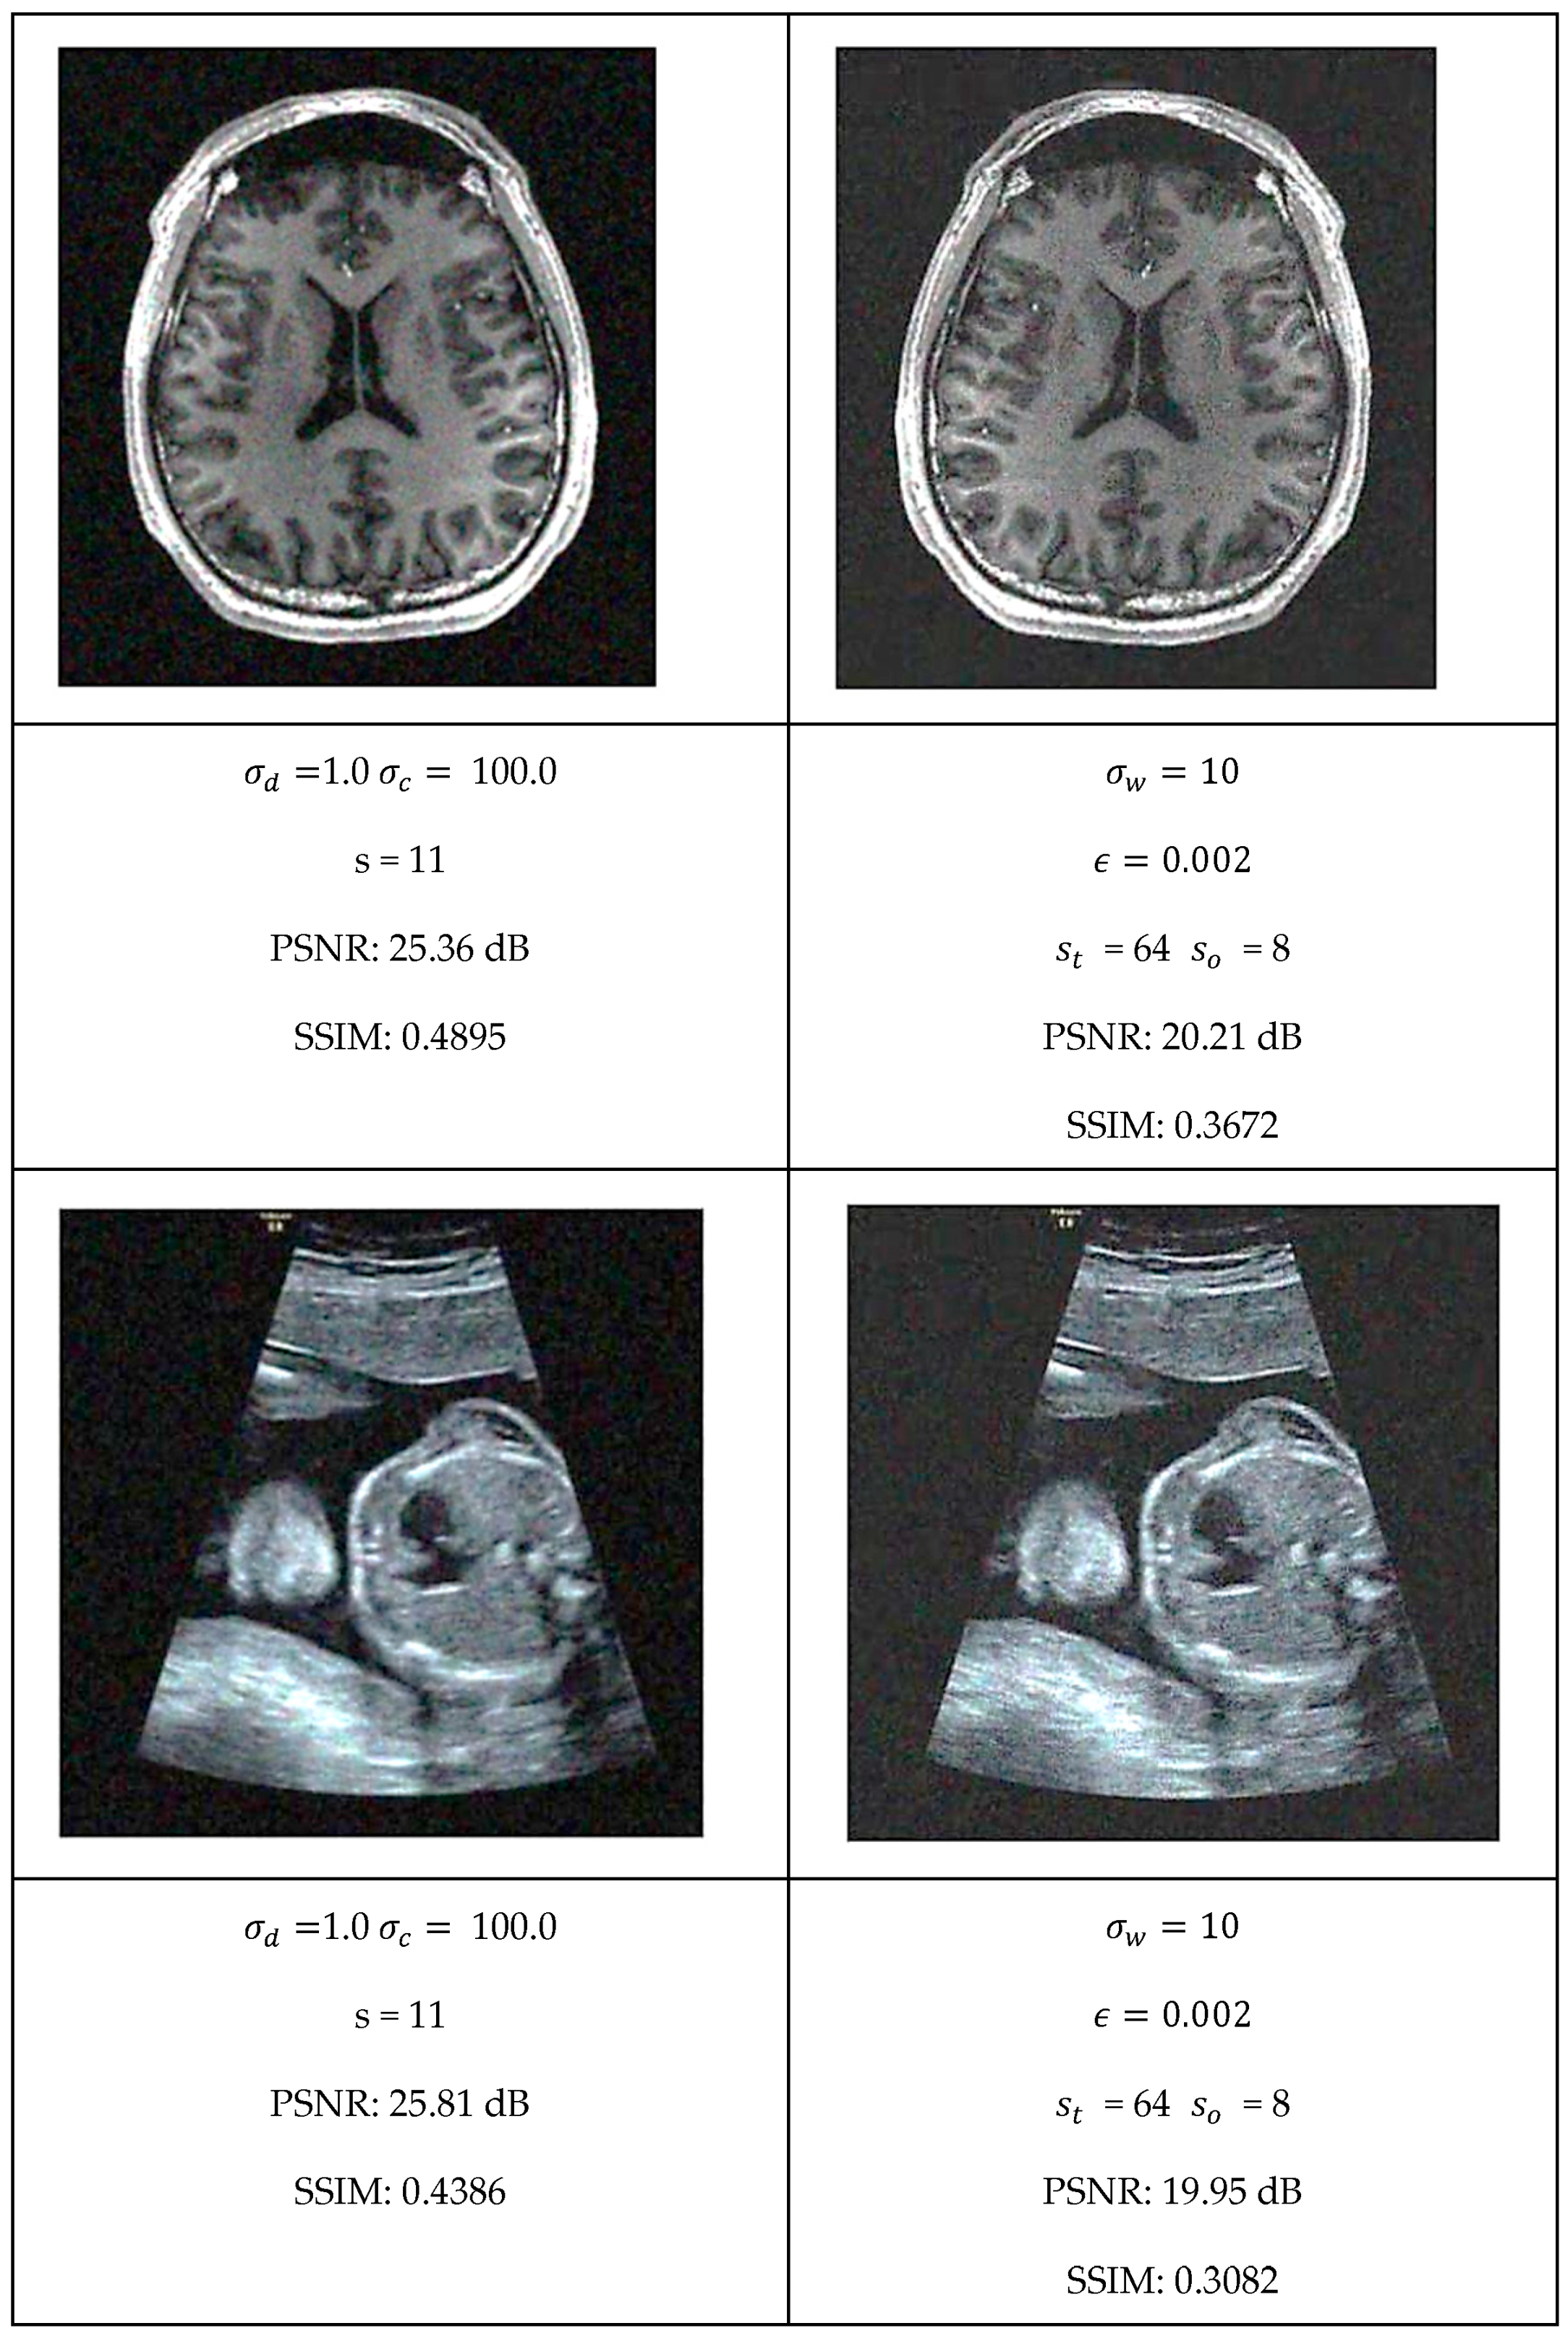

This section presents a comprehensive comparative analysis of our geodesic filtering approach against the state-of-the-art methods. The key to this comparison is based on PSNR and SSIM difference metrics. The noisy images shown in Figure 8 were processed using various implementations of the filtering algorithms described in Section 2. To be fair in our comparison, as with the geodesic filter, we tuned the parameters to produce the best PSNR value possible. The results of this comparison are collected in Figure 9 and Figure 10.

Each algorithm was carefully tuned to achieve optimal performance using the same test image database with standardized noise conditions. For each filter, the tuning parameters are as follows:

• Least Median Filter: window size s and tile size s t ;

• Gradient Anisotropic Diffusion: conductance C and number of iterations #I;

• Curvature Anisotropic Diffusion: the mean curvature of the level sets k and number of iterations #I;

• Bilateral Filter: s kernel size, σ d spatial distance weight, and σ c color distance weight;

• Gaussian Weighted Wavelet DIP Neural Network: σ w Gaussian variance, ϵ minimum tile loss, s t tile size, and s o tile overlap size.